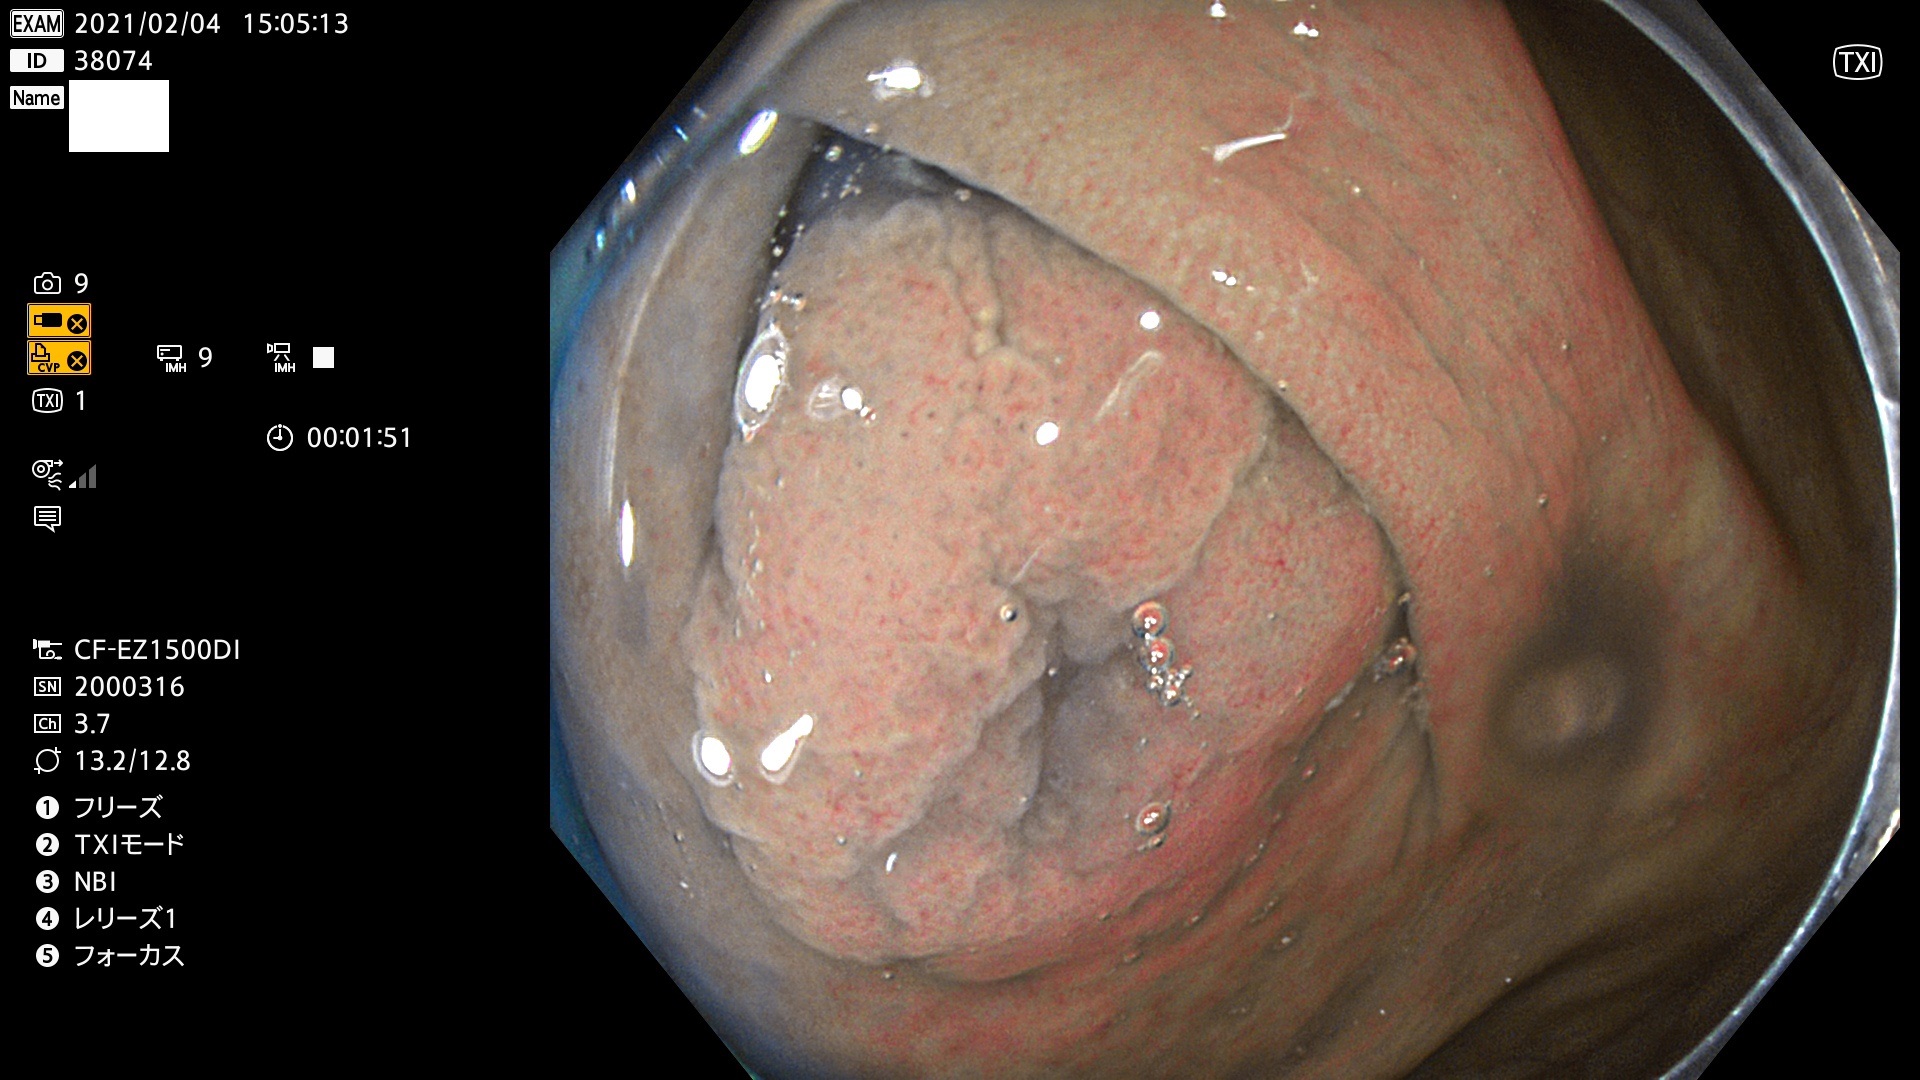

38001 38002 38003 38004 38006(SSAPのみ) 38007 38008 38009 38010 38012 38013 38014 38016 38018 38020 38021 38025 38026 38029 38032 38033 38034 38035 38036 38037(SSAPのみ) 38039 38043 38044 38048 38049 38050 38052 38055 38056 38057 38058 38059 38064(SSAPのみ) 38065 38068 38069 38070 38071 38072 38074 38075 38076 38078 38079 38080 38082 38083 38084 38085(SSAPのみ) 38086 38087 38088 38089 38090 38091 38092 38093 38094 38097 38098 38099

発見困難で危険性の高い平坦型病変(上記100名より抽出)